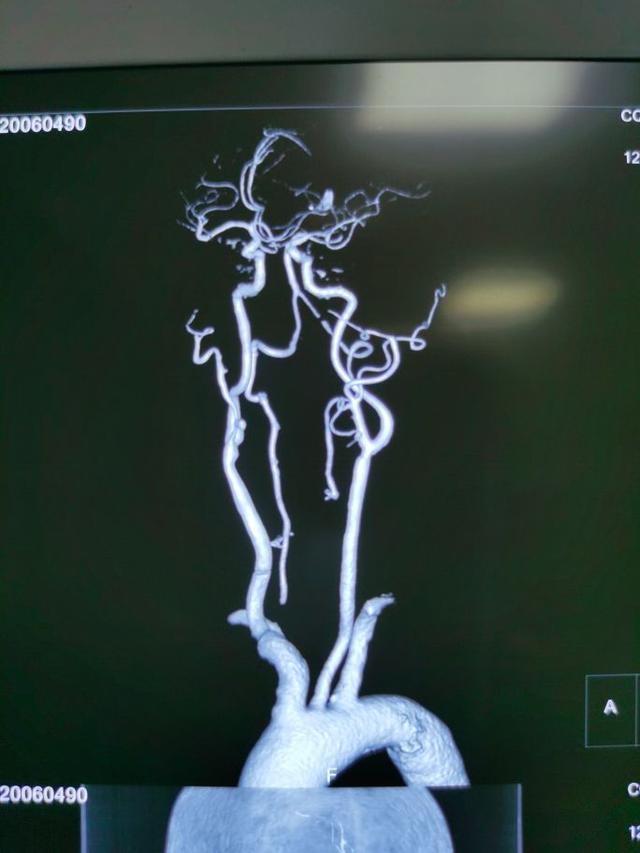

为进一步明确梗死原因,完善头颈CTA

可以看到,患者双侧的椎动脉都有问题!闭塞?狭窄?!为进一步了解血管情况,改善后循环的供血!我们给患者做了脑血管造影: